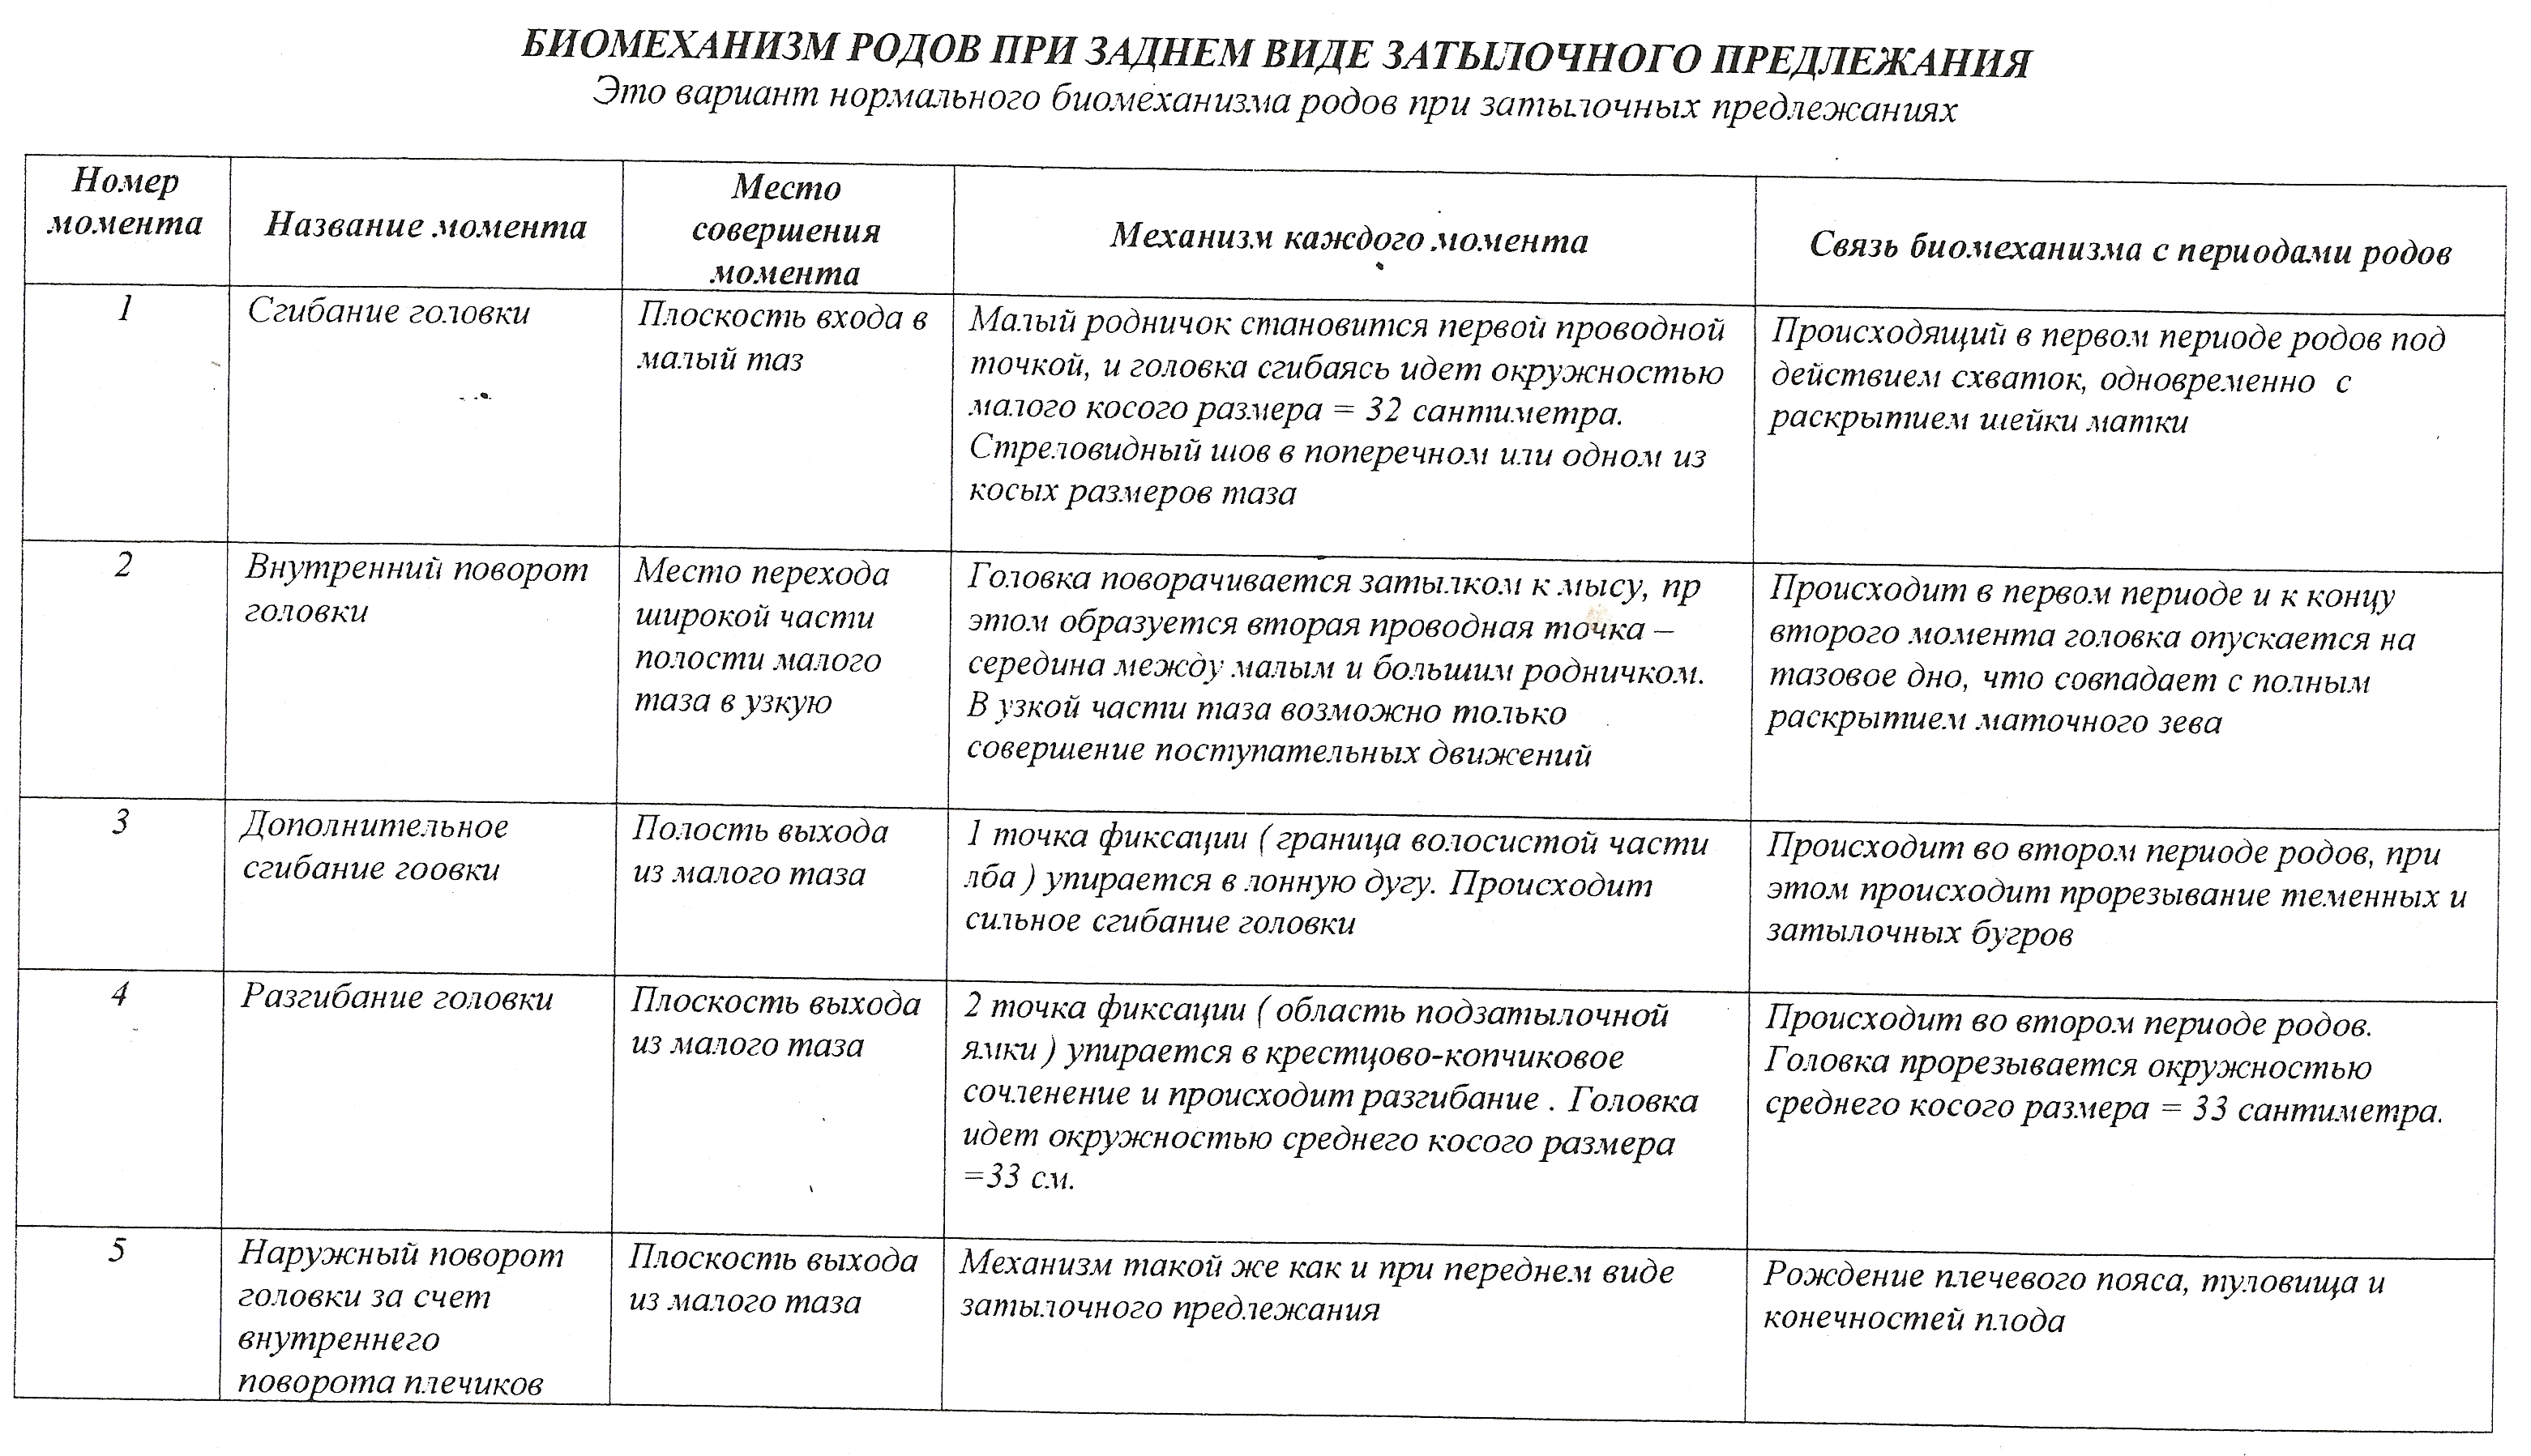

Задний вид затылочного предлежания биомеханизм родов

Биомеханизм родов таблица

Биомеханизм родов таблица